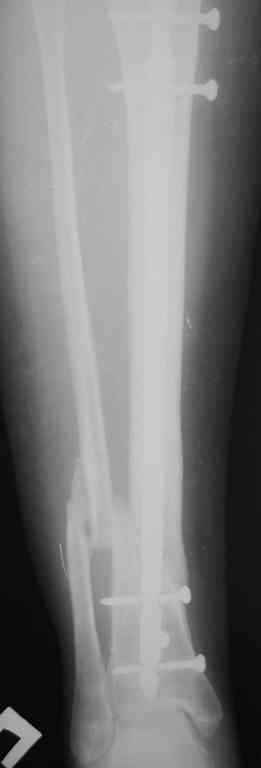

Прилагаются.

Я бы выбрал следующее:

- удаление проксимального куска гвоздя

- остеотомия малоберцовой кости

- внешний остеосинтез в режиме компрессия-дистракция-компрессия.

Да , обсуждалась и оптимальным штифтом был выбран " Мастер" Остеомед 10 мм и винты 5 мм, но увы все наши благие намерения разбились о нашу действительность и материальные возможности больной, обращение ее в страховую компанию и т.д., вообщем выкручивались из внутренних резервов, а они были такими 9 мм штифт Остеомед, под 4 мм винты. Ограничили нагрузку. Ошиблись еще и с оценкой сращения, дали полную нагрузку+ больная поправилась на 18 кг, и вот теперь имеем , что имеем.

Действитльность и возвожности остались прежнее, во внутренних резервах есть 11 мм стержень универсальный ( реконструктивный) "Деост-CHM" много спиц и аппарат + ось конечности и отломок штифта и надежда на Ваши советы.